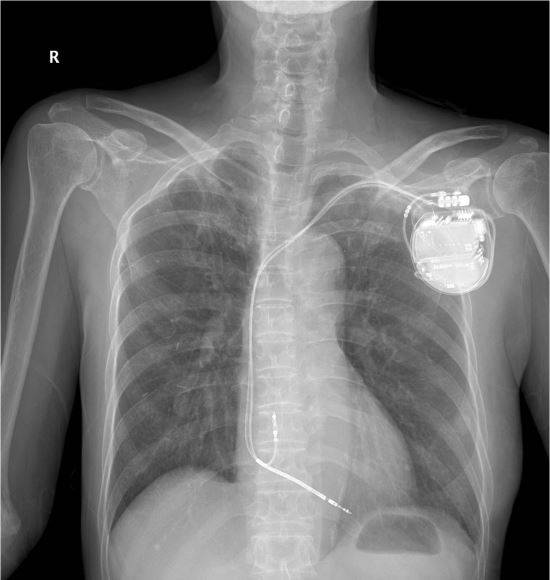

한번 심장정지가 왔던 변이형 협심증은 급사할 확률이 2배 정도 높다는 연구결과가 나왔다. 또 변이형 협심증 환자에게 가슴에 ‘자동 제세동기(심장충격기)’를 삽입하면 사망률을 4분의 1 가량 줄일 수 있는 것으로 나타났다.

또 심장마비 경험 변이 협심증 환자 188명 중 자동 제세동기를 삽입한 24명의 사망률은 4.3%로 제세동기 치료 없이 약물 치료만 시행한 환자 사망률(19.3%)에 비해 4분의 1 정도 낮았다.

삽입형 자동 제세동기는 심각한 부정맥이 있는 환자에서 심장 부근에 기계를 삽입하고 전선을 심장에 연결해 부정맥 발생시 자동으로 전기 충격을 가하는 장치다.